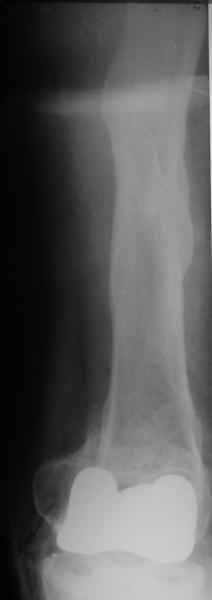

Alexander Chelnokov 02 Июнь 2004, 13:45

В итоге сделали антеградный остеосинтез. В дистракторе свежий перелом вправился сразу, а вот старый - оставил проблему, дистальный отлмомк остался все равно кзади. И гвоздь бы прошел кпереди от него, а ретроградный - перфорировал бы передний кортекс. Так что пришлось еще сделать чрескожную остеотомию через перелом, чтобы малость мобилизовать дистальный отломок. Снимки в прилжении.

Критика, комментарии, мнения?

The radiographs look excellent and a good outcome would be anticipated. The idea to osteotomize the femur shaft to compensate for the prior shaft malunion was clever and should work fine.

I can't actually see the osteotomy on either radiograph. Is it more proximal than we see in these radiographs or so well aligned as to be not visible?

TAC> idea to osteotomize the femur shaft to compensate for the prior shaft malunion

TAC> was clever and should work fine.

The "idea" was an emergency appeared when the nail tip proceeded to the fracture level and became targeting anteriorly to the distal fragment.

TAC> I can't actually see the osteotomy on either radiograph. Is it more proximal

TAC> than we see in these radiographs or so well aligned as to be not visible?

The osteotomy was perfromed trough the fracture site. See the image.